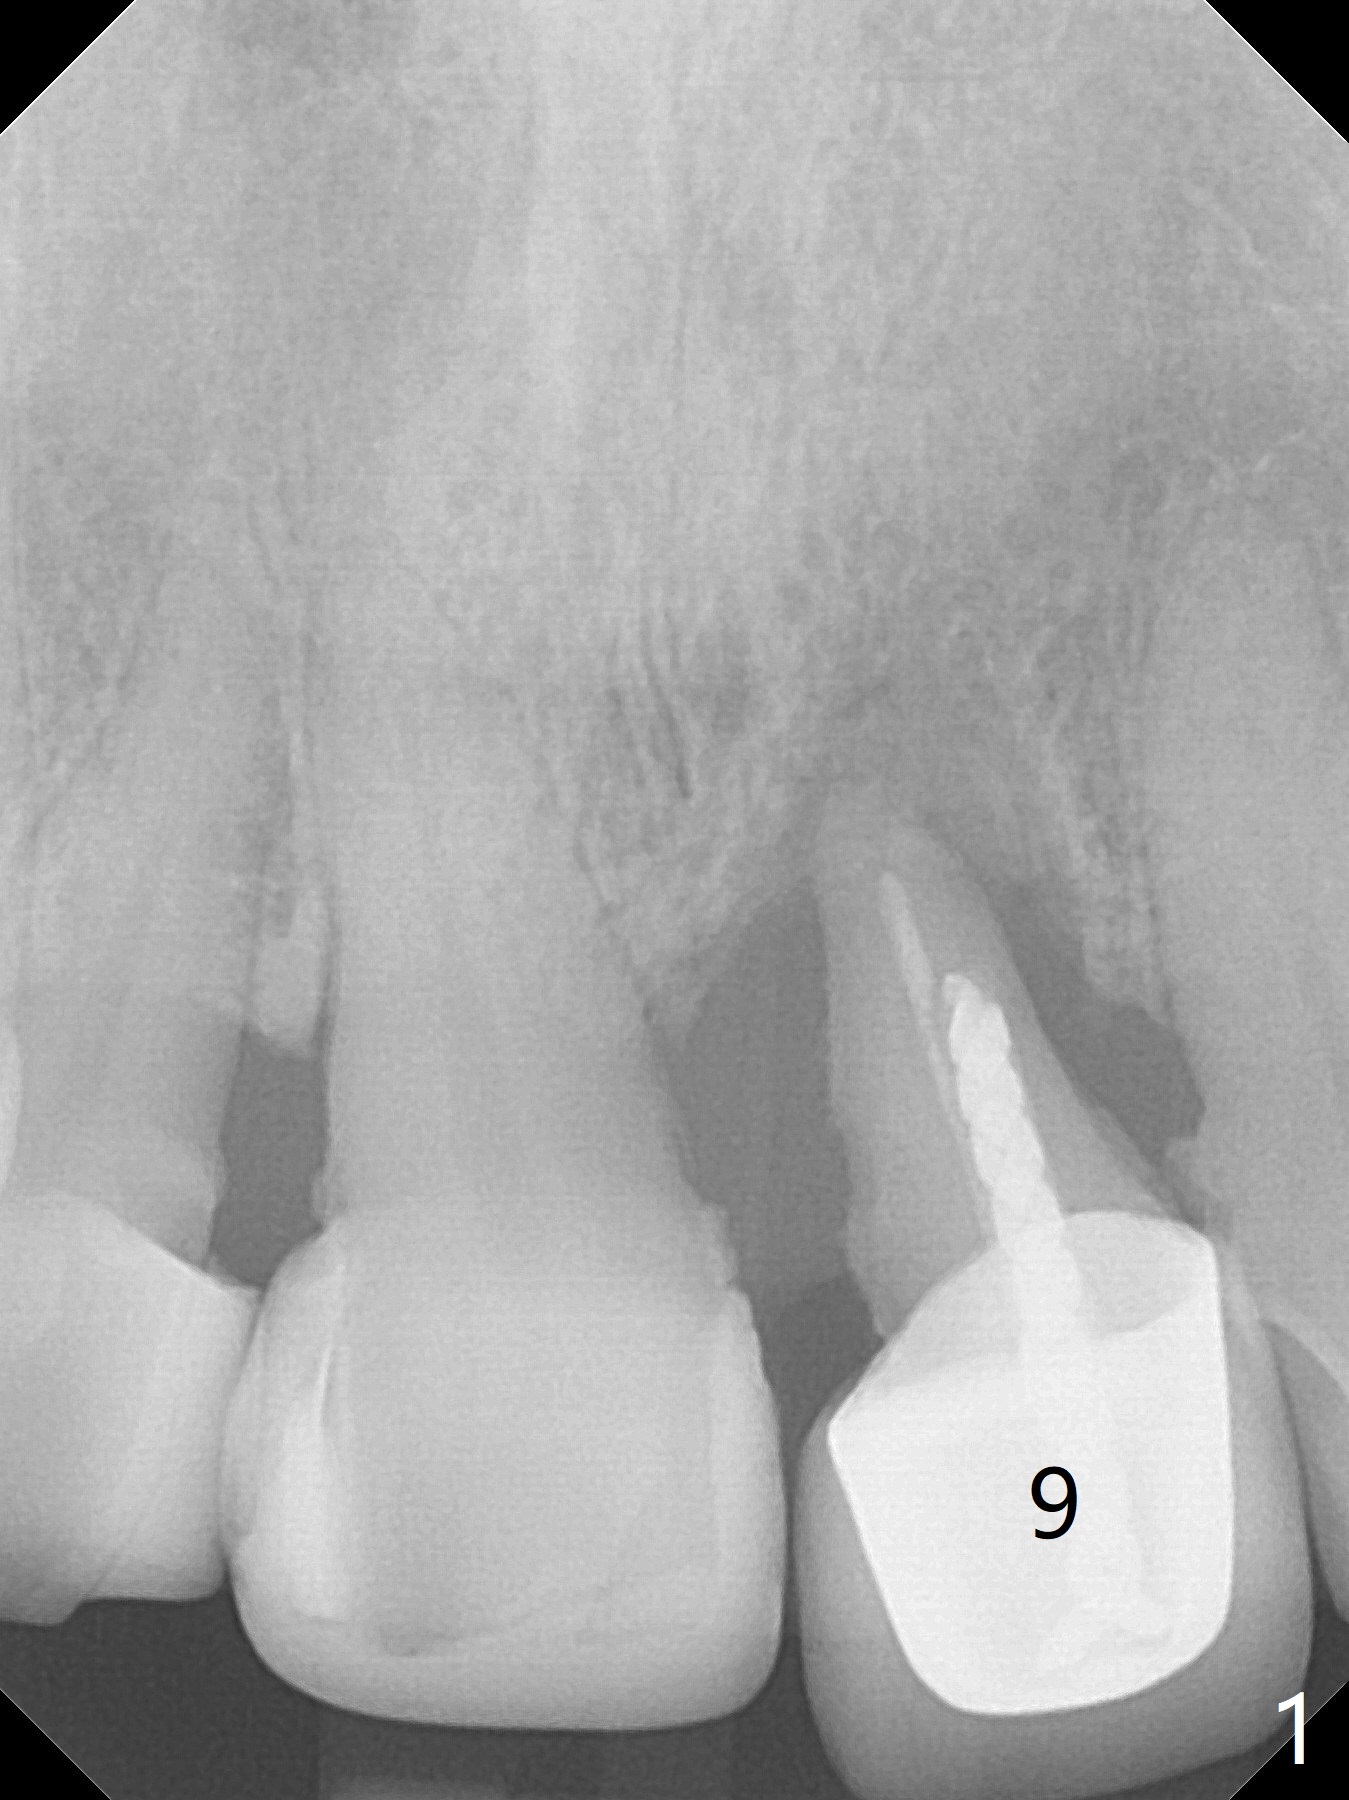

Concern of a 48-year-old woman is the exfoliating central incisor (Fig.1). After SRP (Fig.3,4), a long implant will be placed for stability (Fig.2), considering a posterior missing tooth (Fig.4).